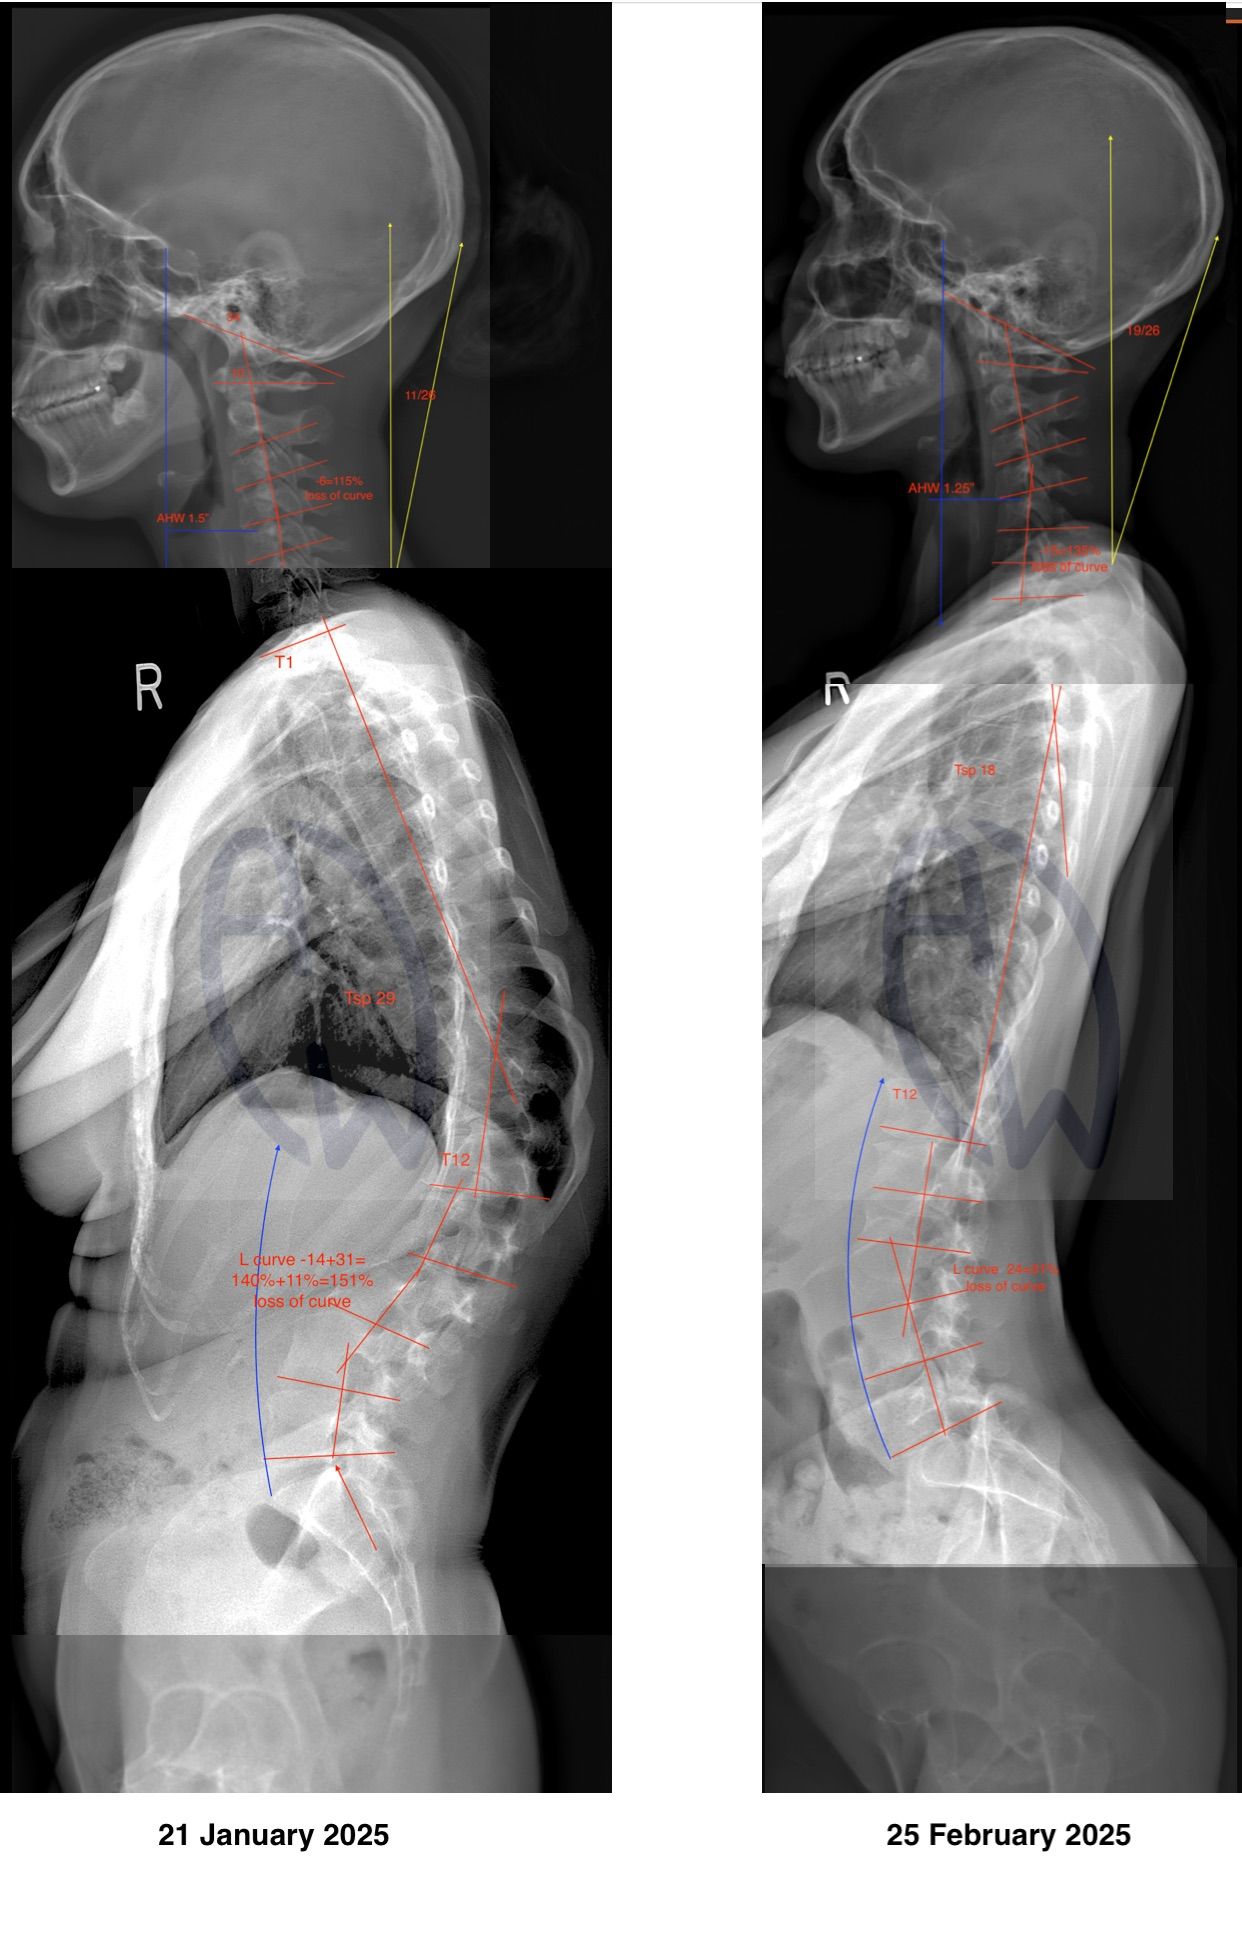

Why Scoliosis Measurements Can Differ Between Practitioners

And Why We Strictly Use Recent X-Ray and Cobb Angle Protocol

It is not uncommon for patients to receive different scoliosis measurements from different practitioners. This can be confusing — and understandably concerning for parents.

2. End Vertebra Selection Matters

The Cobb angle depends on:

• Identifying the most tilted vertebrae at the top and bottom of the curve

• Drawing precise reference lines

Small changes in vertebra selection can alter the measurement by 3–5 degrees, even when viewing the same X-ray.

This is a known and documented inter-observer variability, not error.

3. Standing Position and Weight-Bearing

Scoliosis is a gravity-dependent condition.

• Standing, weight-bearing X-rays show the true functional curve

• Supine or non-weight-bearing imaging often underestimates curvature

This is why we require standing spinal X-rays, not recumbent images.

Why We Insist on Recent X-Ray Imaging

The Theory Behind Cobb Angle Requires Current Data

The Cobb angle is not a static value.

Why We Stand by Our Measurement Protocol

We follow a consistent, repeatable Cobb angle method:

• Same imaging view

• Same weight-bearing position

• Same measurement landmarks

• Same clinical objective: safe, conservative care

This consistency reduces variability and allows:

• Meaningful comparison over time